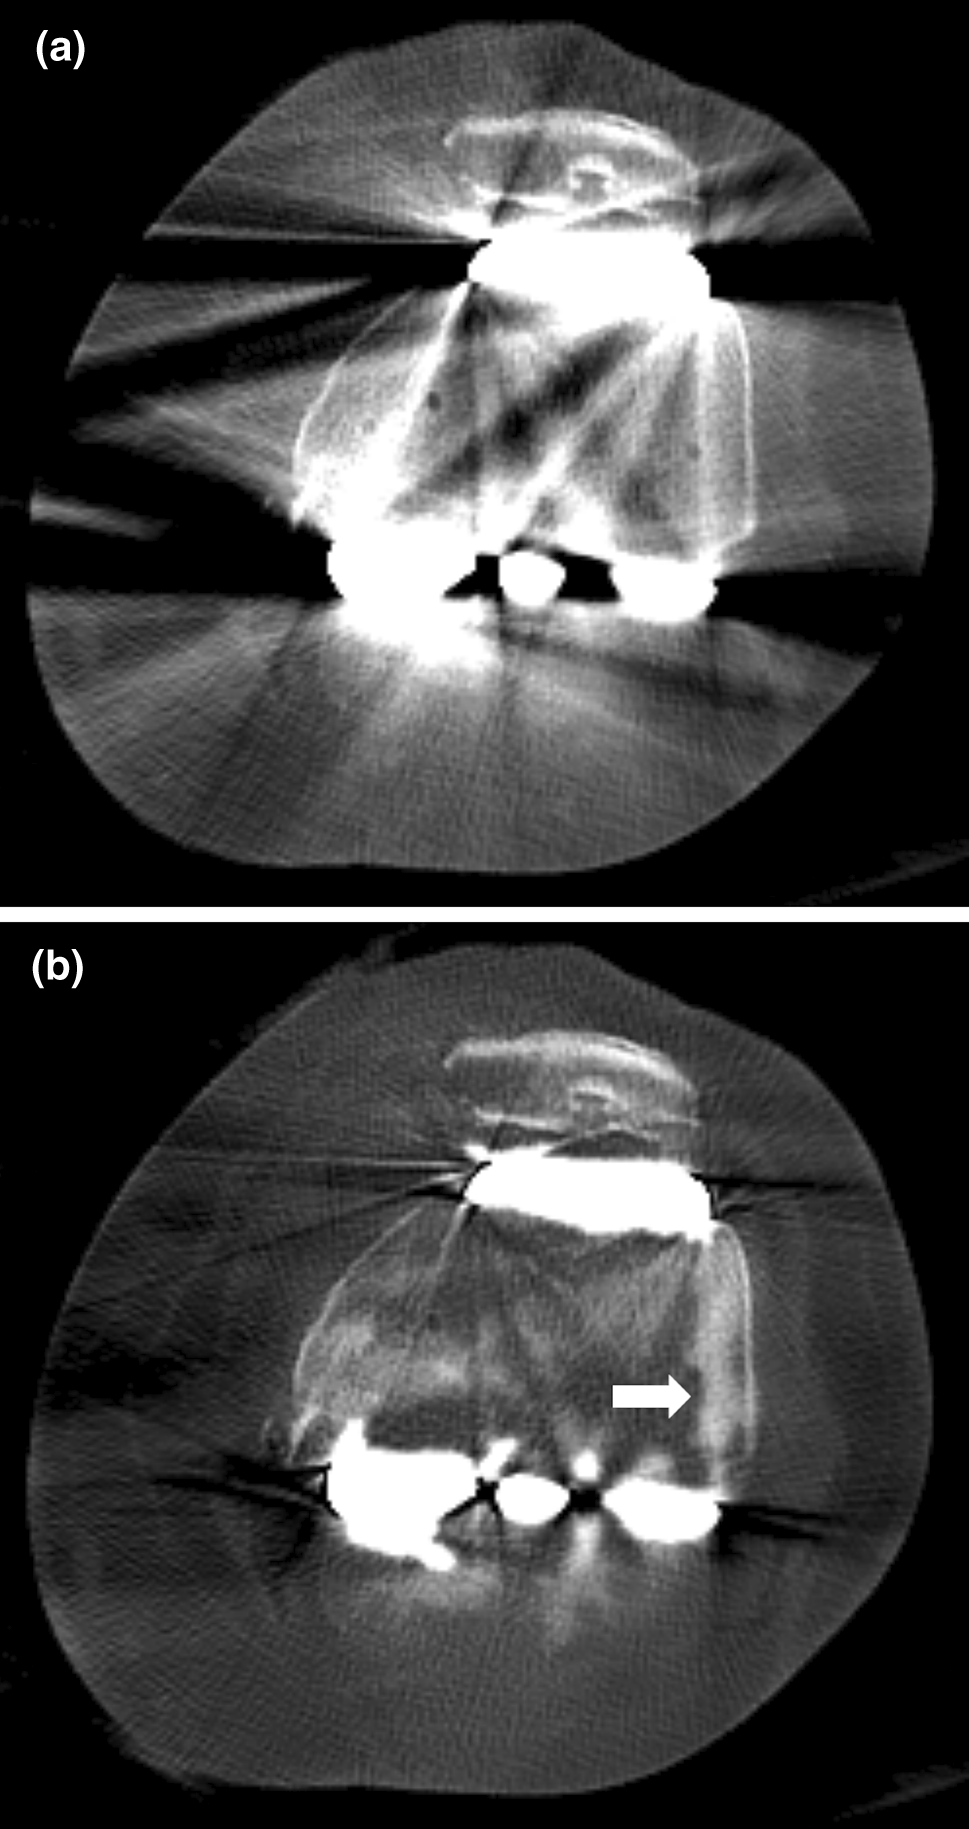

Axial noncontrast CT images of the left knee joint in a 66-year-old woman who underwent total knee arthroplasty. Images were reconstructed using (a) Non-MAR and (b) O-MAR protocols and are shown in the bone window setting (window widthā=ā2000 HU, window levelā=ā500 HU). In the O-MAR image, an abnormally high-attenuated lesion is newly visible adjacent to the lateral femoral condyle, which is not observed in the Non-MAR image. This lesion resembles bone cement and demonstrates a characteristic pseudocement appearance (arrow).